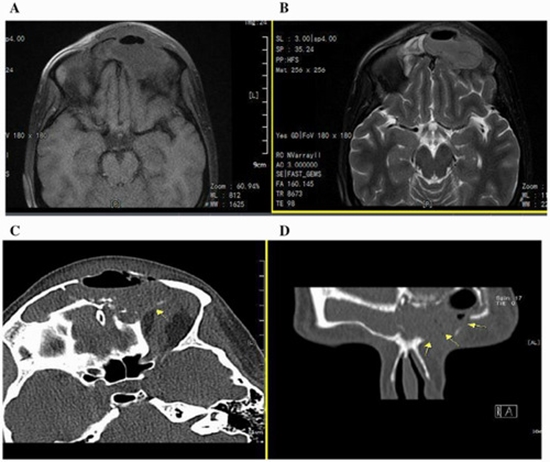

Functional Endoscopic Sinus Surgery in Management of Pott’s Puffy Tumor in a Pregnant Woman: A Clinical Case Report and Literature Review

PPT is a life‐threatening intracranial complication, which is essential to be considered in both children and adults presenting with sinusitis symptoms.